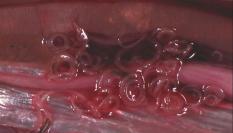

La Agencia Española de Seguridad Alimentaria y Nutrición (AESAN), dependiente del Ministerio de Consumo se refiere con este aviso a un lote de BOQUERONES EN VINAGRE de la marca PESCADOS MEDINA, en el que se ha detectado presencia de anisakis y cuyo consumo ha supuesto la intoxicación leve de al menos tres personas.